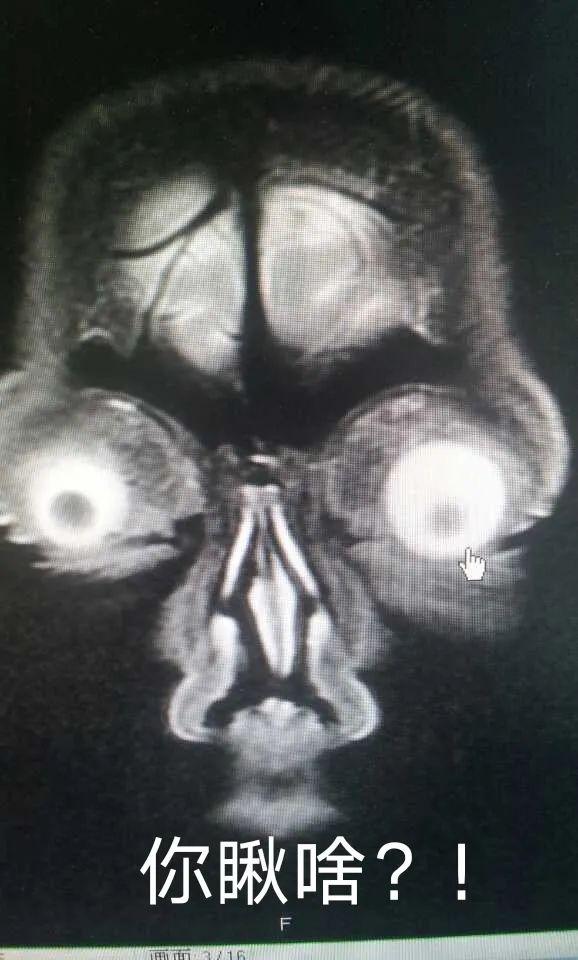

(图为头颅MRI T2相眼球层面横断面)

(图为头颅MRI 冠状位眼球层面切面)